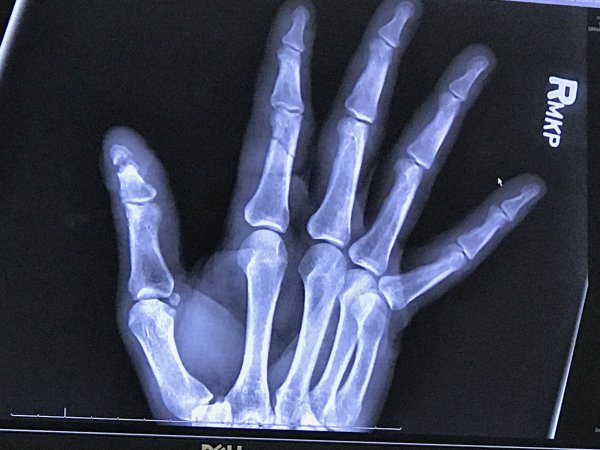

Just don't do this!

A buddy just sent me this. This is 2 weeks post surgery. He got his finger in the way of a splitter helping a buddy split wood.

That is a pin holding the bones together to heal. It will be removed once healed.

When it first happened he captioned these photos with, "apparently I'm not as good with this whole wood splitting thing as you are". LOL He said the finger was just hanging.